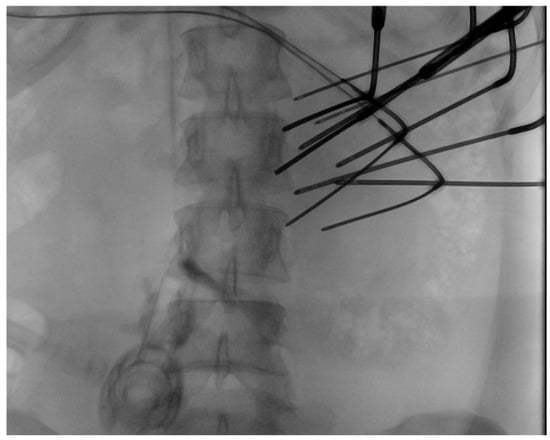

| Number of probes | 10 | 19 | 13 |